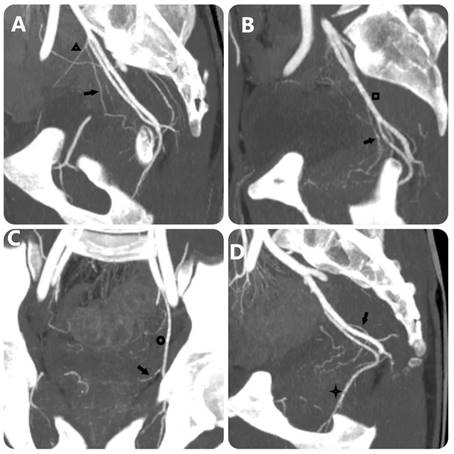

Figure 2

MIP images with 10-mm slice thickness image PA's origin equivalent FC Carnervale's classification: (a) type 1, (b) type 2, (c) type 3, and (d) type 4. (Black arrow: prostate artery, black triangle: superior vesical artery, black square: anterior trunk of internal iliac artery, black circle: obturator artery, black star: internal pudendal artery).

Evaluation of the group 2 in the study included 50 patients who received DECT scans before embolization to treat BPH. The results showed that the ability to detect PA on DECT was almost equivalent to DSA with a detection rate of 96.15%, no false positives, false negative rate of 3.85%. The study of Maclean et al. [18] evaluated the value of CTA in identifying the PA and the anastomoses, showing that the detection rate of the PA was 97.3%, equivalent to the results of our study. Author Kim et al. [4] evaluated the effectiveness of MRA in determining the origin of the PA before the intervention, the results showed that 26/34 PAs were identified (accounting for 76.5%) in 17 patients. In addition, in our study, the PA originating from the common trunk with superior vesical artery accounted for the highest proportion (33.2%), and the PA originating from the obturator artery was the second most common. Research by author Nguyen Xuan Hien[16] showed similar results, the most common location was from the common trunk with superior vesical artery (33.1%) and the second most common location was from the internal pudendal artery. On DECT images, determining the origin of the PA is based on the image of the artery's path from the glandular parenchyma towards the origin, due to the ability to construct MIP and 3D images and locate points on planes (Fig. 2) (Fig. 3). In addition, less common locations of origin of the PAs are the superior gluteal artery (SGA), inferior mesenteric artery (IMA), middle rectal artery, accessory internal pudendal artery (IPA), accessory obturator artery (OA), or others. In our study, the rate of rare locations (type V) was 6%, equivalent to FC Carnervale's classification [6]. In cases where the PA cannot be found when selecting the arterial branches internal iliac, especially when the ipsilateral obturator artery is not observed, then angiography of the external iliac artery should be performed to find the PA separating from the accessory obturator artery (OA) (Fig. 3). In this case, the interventionist should not let the embolization material reflux out of the PA because there is a lower limb artery occlusion risk. In addition, the PA variant originating from the accessory pudendal artery is considered the most important variant in the type V variant group because the accessory pudendal artery often has a parallel path and connects with the internal pudendal artery, so it is often very short and prone to reflux when injecting paralysis material. To avoid non-target embolization in the penile area, it is necessary to use a coil or sponge to block this connection [19]. Our study encountered 03 cases of PA originating from the accessory pudendal artery with a rate of 0.8%. DECT imaging to evaluate the PA before intervention will be helpful in pre-identifying these rare cases, helping to reduce the time to select the PA. In addition, our study also found that there was asymmetry in the origin of the pelvic artery on both sides of the pelvis in the same patient in 74.3%, similar to the study of author Wang [11]. This suggests that each side of the pelvis should be considered independent when selective arterial catheterization and embolization are performed.